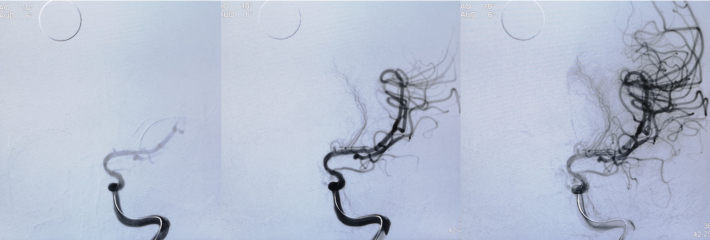

3mm*15mm球囊扩张

球囊扩张后